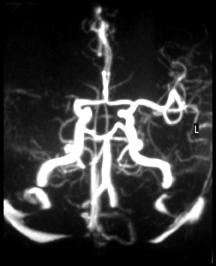

Here are 3 angiograms. Each case represents either a thrombotic, hypoperfusion, and hemorrhagic stroke. Which is which?

What would thrombosis of an artery look like on an angiogram?

What is a precursor lesion that can lead to cerebral hemorrhage and what might it look like?

In the absence of hemorrhage or thromboembolic event, would you expect to see any abnormality on the angiogram (assuming the patient recovered)?